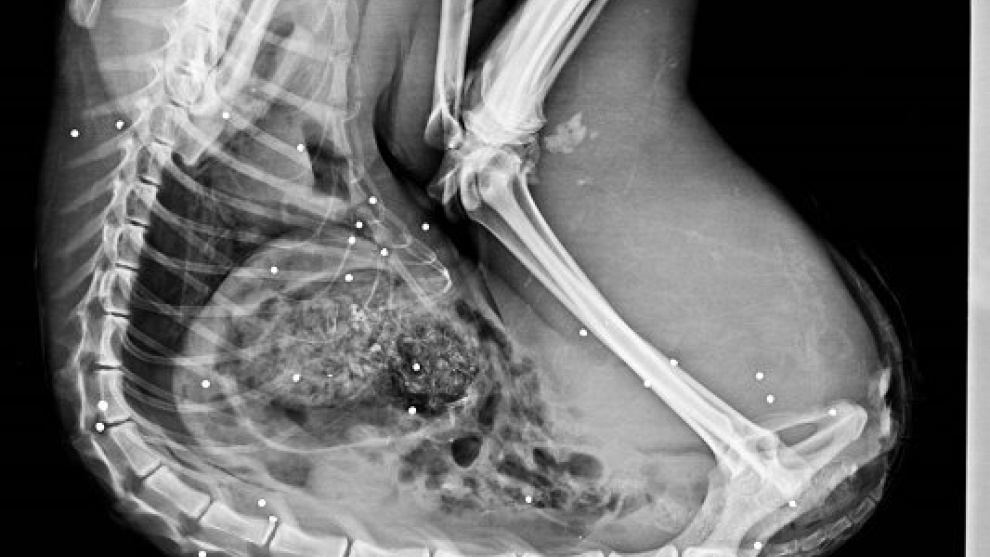

En 2017 han muerto 34 linces en España por la acción humana

El cuerpo del animal fue identificado por los técnicos, que tras un primer análisis ocular, no apreciaron indicios de violencia. Fue trasladado al Centro de Análisis y Diagnóstico de la Fauna Silvestre de la Junta de Andalucía (CAD) donde se le está practicando la necropsia. Según han desvelado los primeros datos de la misma, en el cuerpo de esta lince se han observado unos 35 plomos, lo que viene a constatar que detrás de esta muerte está la acción humana.